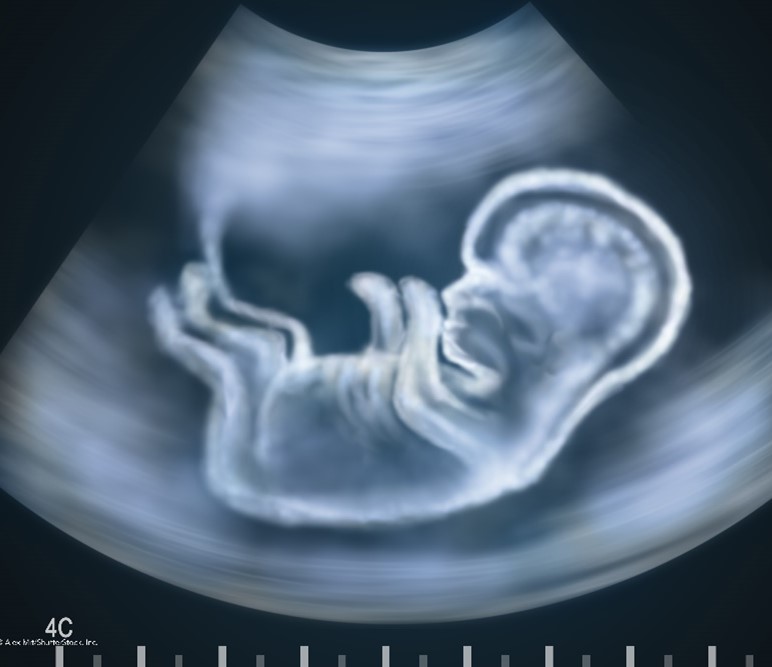

Ultrasound